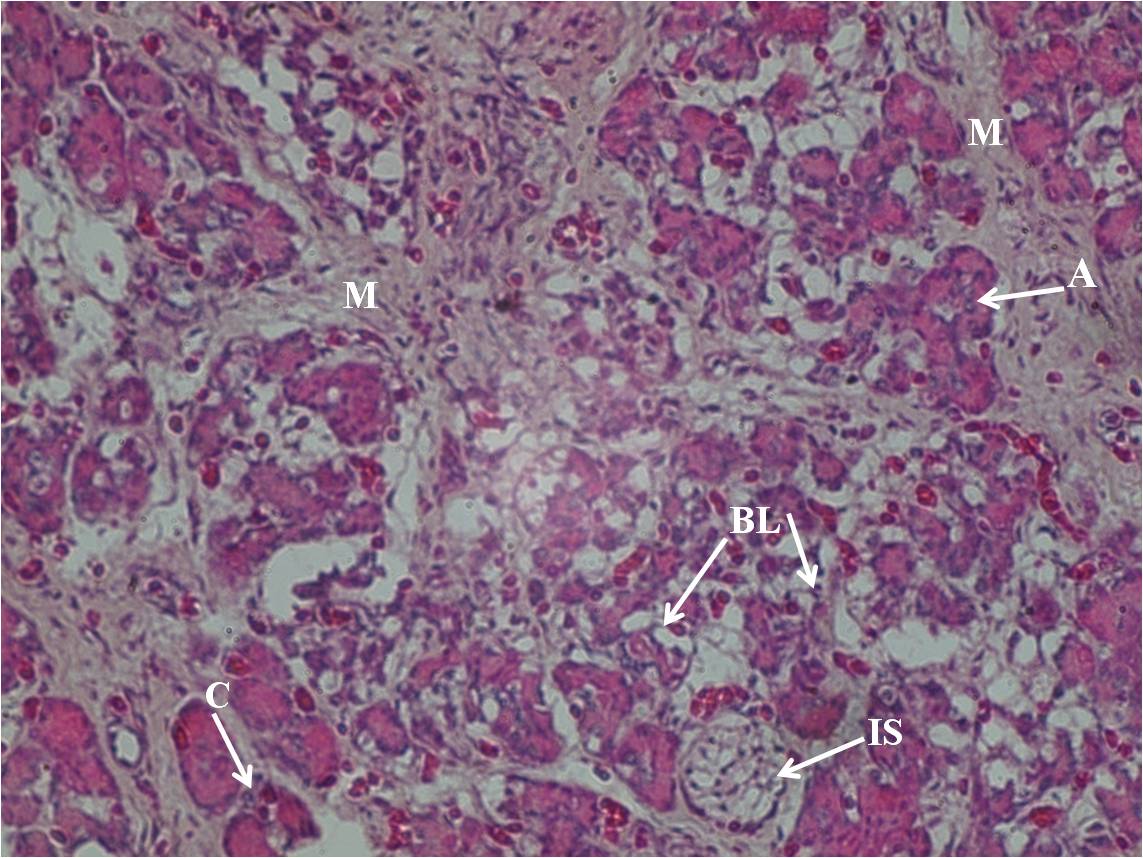

Material and Methods: Forty nine fetuses were collected in formal saline immediately after abortion, medical termination of pregnancy or premature delivery. The fetal pancreas was processed for paraffin blocks. Sections were taken and stained with Haematoxylin and Eosin as well as Gomori’s modified Aldehyde Fuchsin stain and observed under light microscope.

Results: Islets were initially a small number of cells with Alpha cells, which were seen at 10th week of gestation. Beta cells were identified in the islets of fetuses around 16 weeks of gestation. Delta cells were observed from 17 weeks onwards and islets appeared as a group from the beginning of 19th week.